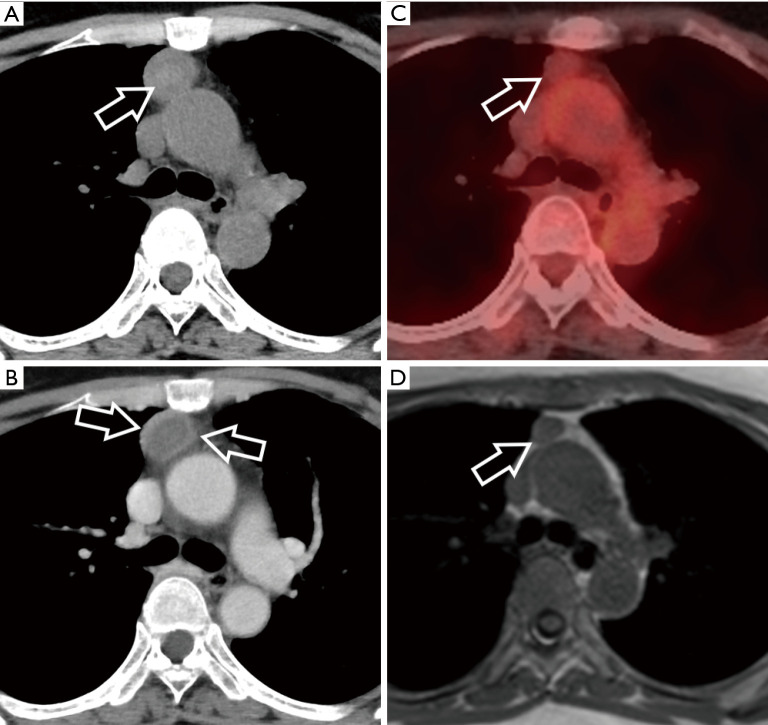

这篇综述文章全面探讨了胸腺上皮性肿瘤 (TET) 和其他纵隔肿块的诊断方法,重点是成像模式和鉴别诊断。文章首先讨论了纵隔肿瘤的传统和现代分类系统,包括日本胸腺研究协会(JART)和国际胸腺兴趣小组(ITMIG)的分类,然后强调了向基于计算机断层扫描(CT)分类的转变。重点强调了区分前纵隔实性和囊性病变的重要性,并详细介绍了胸腺瘤、胸腺癌和胸腺神经内分泌肿瘤(NET)等各种 TET 亚型的影像学特征和组织学特征。该综述还阐明了常见的鉴别诊断,包括淋巴瘤和生殖细胞瘤,为准确诊断的关键影像学发现和注意事项提供了指导。此外,书中还强调了患者背景和血液检查在鉴别诊断中的重要性,并讨论了与年龄相关的发病模式和肿瘤标志物评估。在探讨了胸腺囊肿给诊断带来的挑战,对其放射学特征、管理注意事项和潜在并发症提出见解后,本综述扩展到其他罕见纵隔病变,强调了对这些肿瘤进行准确识别和管理的全面评估的必要性。最后,作为示例,我们介绍了六个病例,着重说明包括 TET 在内的前纵隔肿瘤的各个方面。这些病例为临床实践中遇到的诊断难题、影像学特征和管理注意事项提供了宝贵的见解。本文介绍的病例并不都是典型的图像、病程和诊断。但是,每个病例都具有重要意义。因此,我们在介绍这些病例时,相信它们有助于理解实际临床实践中影像诊断的复杂细微差别。

This review article comprehensively examines the diagnostic approach to thymic epithelial tumors (TETs) and other mediastinal masses, focusing on imaging modalities and differential diagnosis. Beginning with a discussion on traditional and contemporary classification systems for mediastinal tumors, including the Japanese Association for Research on the Thymus (JART) and International Thymic Interest Group (ITMIG) classifications, it highlights the shift towards computed tomography (CT)-based categorizations. Emphasis is placed on the importance of distinguishing between solid and cystic lesions in the anterior mediastinum, with detailed insights into imaging characteristics and histological features of various TET subtypes such as thymomas, thymic carcinomas, and thymic neuroendocrine tumors (NETs). The review also elucidates common differential diagnoses, including lymphomas and germ cell tumors, providing guidance on key imaging findings and considerations for accurate diagnosis. Furthermore, it underscores the significance of patient background and blood tests in differential diagnosis, discussing age-related prevalence patterns and tumor marker assessment. After addressing the diagnostic challenges posed by thymic cysts offering insights into their radiological features, management considerations, and potential complications, this review extends to other rare mediastinal lesions highlighting the need for a comprehensive evaluation for accurate identification and management of these tumors. Finally, as illustrative examples, we present six cases highlighting various aspects of anterior mediastinal tumors, including TET. These cases provide valuable insights into the diagnostic challenges, imaging characteristics, and management considerations encountered in clinical practice. The cases presented herein do not all illustrate typical images, courses, and diagnoses. However, they each contain significant implications. Thus, we present them with the belief that they will aid in understanding the intricate nuances of image diagnosis in actual clinical practice.